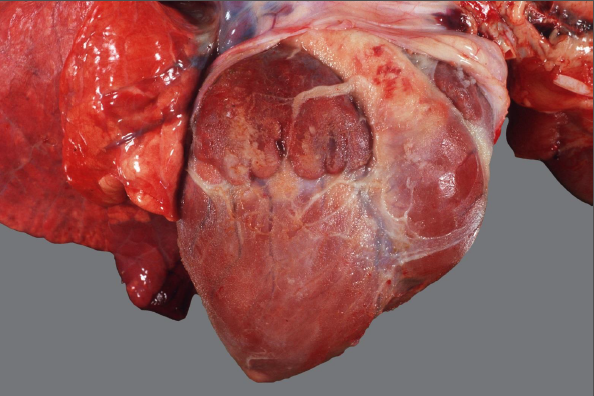

Schwein, Herz: Hochgradige, diffuse, subakute fibrinöse und fibroblastische Peri- und Epikarditis

Herz mit seröser Atrophie

- fibrinöse Epicarditis

- fibrosierende Pericarditis

Gehört zu der angeschnittenen Lunge dazu

Rind, Herz/Trikuspidalklappe: Hochgradige, chronisch-aktive, multifokale, fibrinös-eitrige Endocarditis valvularis

Beschreibung:

auf der Trikuspidalklappe lassen sich multiple, blumenkohlartige Verdickungen, sowie Aufrauungen und Ulzerationen

des Klappenendothels darstellen.

Es sind dunkelrot-gelbe, unregelmäßig geformte

Fibrinauflagerungen auf und zwischen den Verdickungen zu erkennen

Hintergrundwissen/ Infektionsweg/ Pathogenese

prinzipiell bei allen Tieren, am häufigsten betroffen sind Rind (Trikuspidalis) und Schwein (Mitralis), selten bei Hund (Mitralis) und Pferd (Aortenklappe)

selten vollständige Regeneration, durch Strömung und mechanische Kräfte eher sich selbst erhaltender Entzündungsprozess, intraläsionale Bakterien sind nicht immer nachweisbar

Infektionswege/Pathogenese:

genauer Mechanismus bislang nicht vollständig geklärt (evtl. Vorschädigung durch Traumata, Sepsis, Arbeitsüberlastung)

Folge einer bakteriämischen Infektion, Endothelschäden (z.B. bakteriell-toxisch) und Thrombusbildung (i.S. Virchow-Trias)

Anhaftung an den Klappen i.F. von begünstigenden Strömungsverhältnissen und spezifischer Bakterien-Endothel-Wechselwirkung (z.B. Erysipelothrix rhusiopathiae)

Vegetativer (d.h. veränderlicher) Entzündungscharakter, fibrinös-eitrige Charakteristika gehen z.B. mit steigender Chronizität in eitrig-granulierende über

Erreger (exemplarisch):

Trueperella pyogenes (Rd.), E. rhusiopathiae (Schw.), Streptococcus spp., Staphylococcus spp. (Flfr. & Pfd.)

Komplikationen:

Mitralis: Thrombembolien (Niereninfarkte, embolisch-eitrige Herdnephritis, Stauungslunge); Trikuspidalis: Lungenembolie, embolisch-eitrige

Pneumonie, Aszites, Stauungsleber

DD für Herzklappenveränderungen: Endokardiose (Hd.), Klappenzysten, Klappenamyloidose (Rd.)